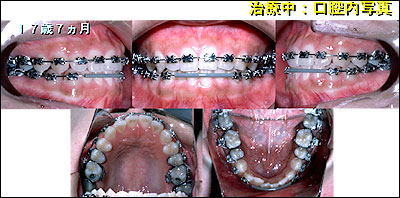

経過観察中に上下顎右側の側切歯の反対被蓋を主訴に矯正治療を希望されました。

エッジワイズ法(レベル アンカレッジ システム)にて、矯正治療を開始しました。 |

| 治療期間は17ヶ月で、その後保定・観察をおこなっています。 |